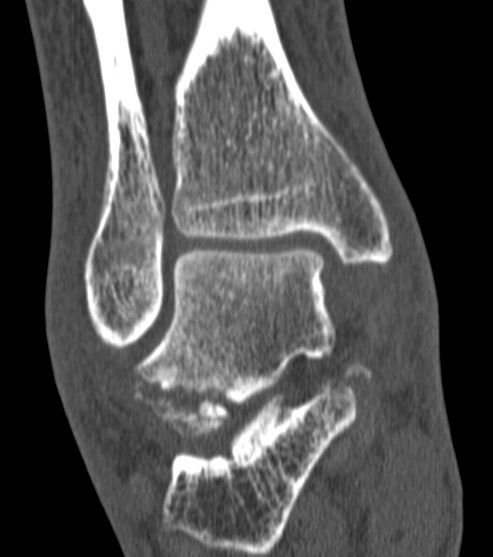

CT

McCrory-Bladin Classification

| Type I |

Type 2A |

Type 2B | Type 3 |

Chip fracture Doesn't involve articular surface |

Larger fracture Involves articular surface talofibular & subtalar join Undisplaced |

Larger fracture Involves articular surface talofibular & subtalar joint Displaced |

Comminuted fracture Involves articular surface talofibular & subtalar |